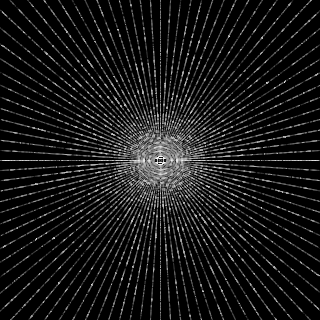

This article presents a novel undersampled magnetic resonance imaging (MRI) technique that leverages the concept of Neural Radiance Field (NeRF). With radial undersampling, the corresponding imaging problem can be reformulated into an image modeling task from sparse-view rendered data; therefore, a high dimensional MR image is obtainable from undersampled $k$-space data by taking advantage of implicit neural representation. A multi-layer perceptron, which is designed to output an image intensity from a spatial coordinate, learns the MR physics-driven rendering relation between given measurement data and desired image. Effective undersampling strategies for high-quality neural representation are investigated. The proposed method serves two benefits: (i) The learning is based fully on single undersampled $k$-space data, not a bunch of measured data and target image sets. It can be used potentially for diagnostic MR imaging, such as fetal MRI, where data acquisition is relatively rare or limited against diversity of clinical images while undersampled reconstruction is highly demanded. (ii) A reconstructed MR image is a scan-specific representation highly adaptive to the given $k$-space measurement. Numerous experiments validate the feasibility and capability of the proposed approach.